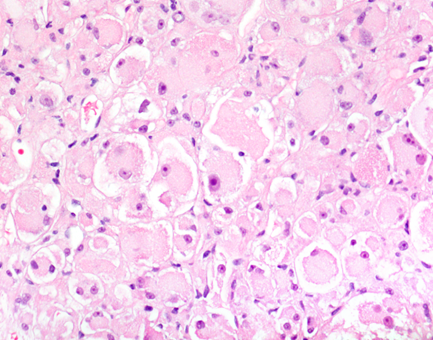

| Figure 2. H&E (400X) |

The liver biopsy showed an infiltrative neoplastic process with a solid to vaguely organoid growth pattern. The tumor was composed of large plump cells showing an epithelioid and plasmacytoid appearance. The tumor cells had abundant eosinophilic cytoplasm with low nuclear to cytoplasmic ratios and frequent multinucleated giant cells. Mitotic figures were rare. Necrosis was not detected. The background liver exhibited no features of chronic hepatitis or cirrhosis.

Grossly the tumor occurs as a yellow to gray mass, which may reach up to 20 cm in size. Microscopically, PEComas are composed of clear to slightly eosinophilic cells that grow in distinctive nested or sometimes sheet-like patterns. The cells organize in a radial fashion around blood vessels. The blood vessel types range from thin spider web-like capillary networks to dilated, hyalinized, thick-walled arterioles. Both epithelioid and myoid elements are prominent, with the epithelioid cells typically occupying the more immediate perivascular space and the spindle-shaped myoid cells farther away. Multinucleated giant cells are characteristic. Many cells may demonstrate cytoplasmic distention with glycogen or lipid. PEComas are generally considered benign neoplasms, if they lack malignant morphologic features. Tumors that are “symplastic” or large in size are considered uncertain in terms of malignant potential. The dimorphic cellular composition of this tumor makes fine needle aspiration and core biopsy diagnosis difficult as it was witnessed in our case. Higher grade and cellularity correspond to higher malignant potential. If more than two “worrisome” histologic features are identified, the tumor is considered malignant.